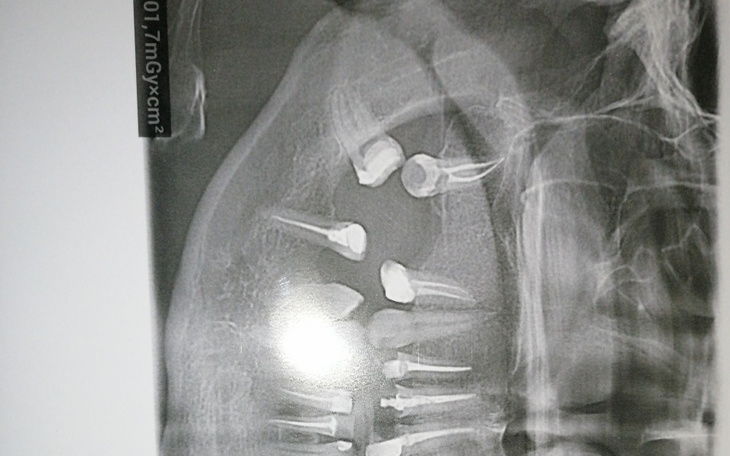

Mam problem od nastoletnich lat, większośc zębów mam niestety przeleczonych kanałowo,a wiadomo jakie to są zęby, ciemne słabe, w tej chwili mam większość dosztukowane, ale w tej chwili sytuacja jest bardzo zła.

Mam 6 braków zębów i 3 sztuczne. Jeśli nie wzmocnie swoich i nie dołożę sztucznych, nawet już nie marzę o implantach, wystarczą mi mosty byleby w końcu móc się normalnie uśmiechnąć.